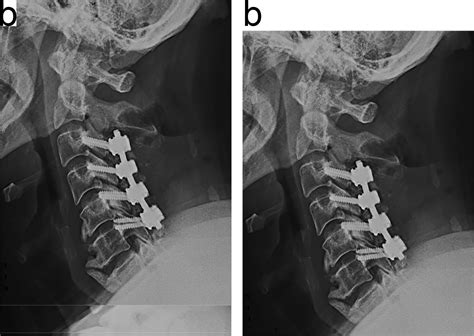

The fusion component involves connecting two or more vertebrae permanently. Using bone grafts, metal rods, and screws, the surgeon facilitates a biological process where the bones grow together into a single, solid unit. This prevents painful movement between the vertebrae and provides the support necessary to prevent future spinal instability.

The Surgical Experience and Recovery

• laminectomy with fusion and fixation